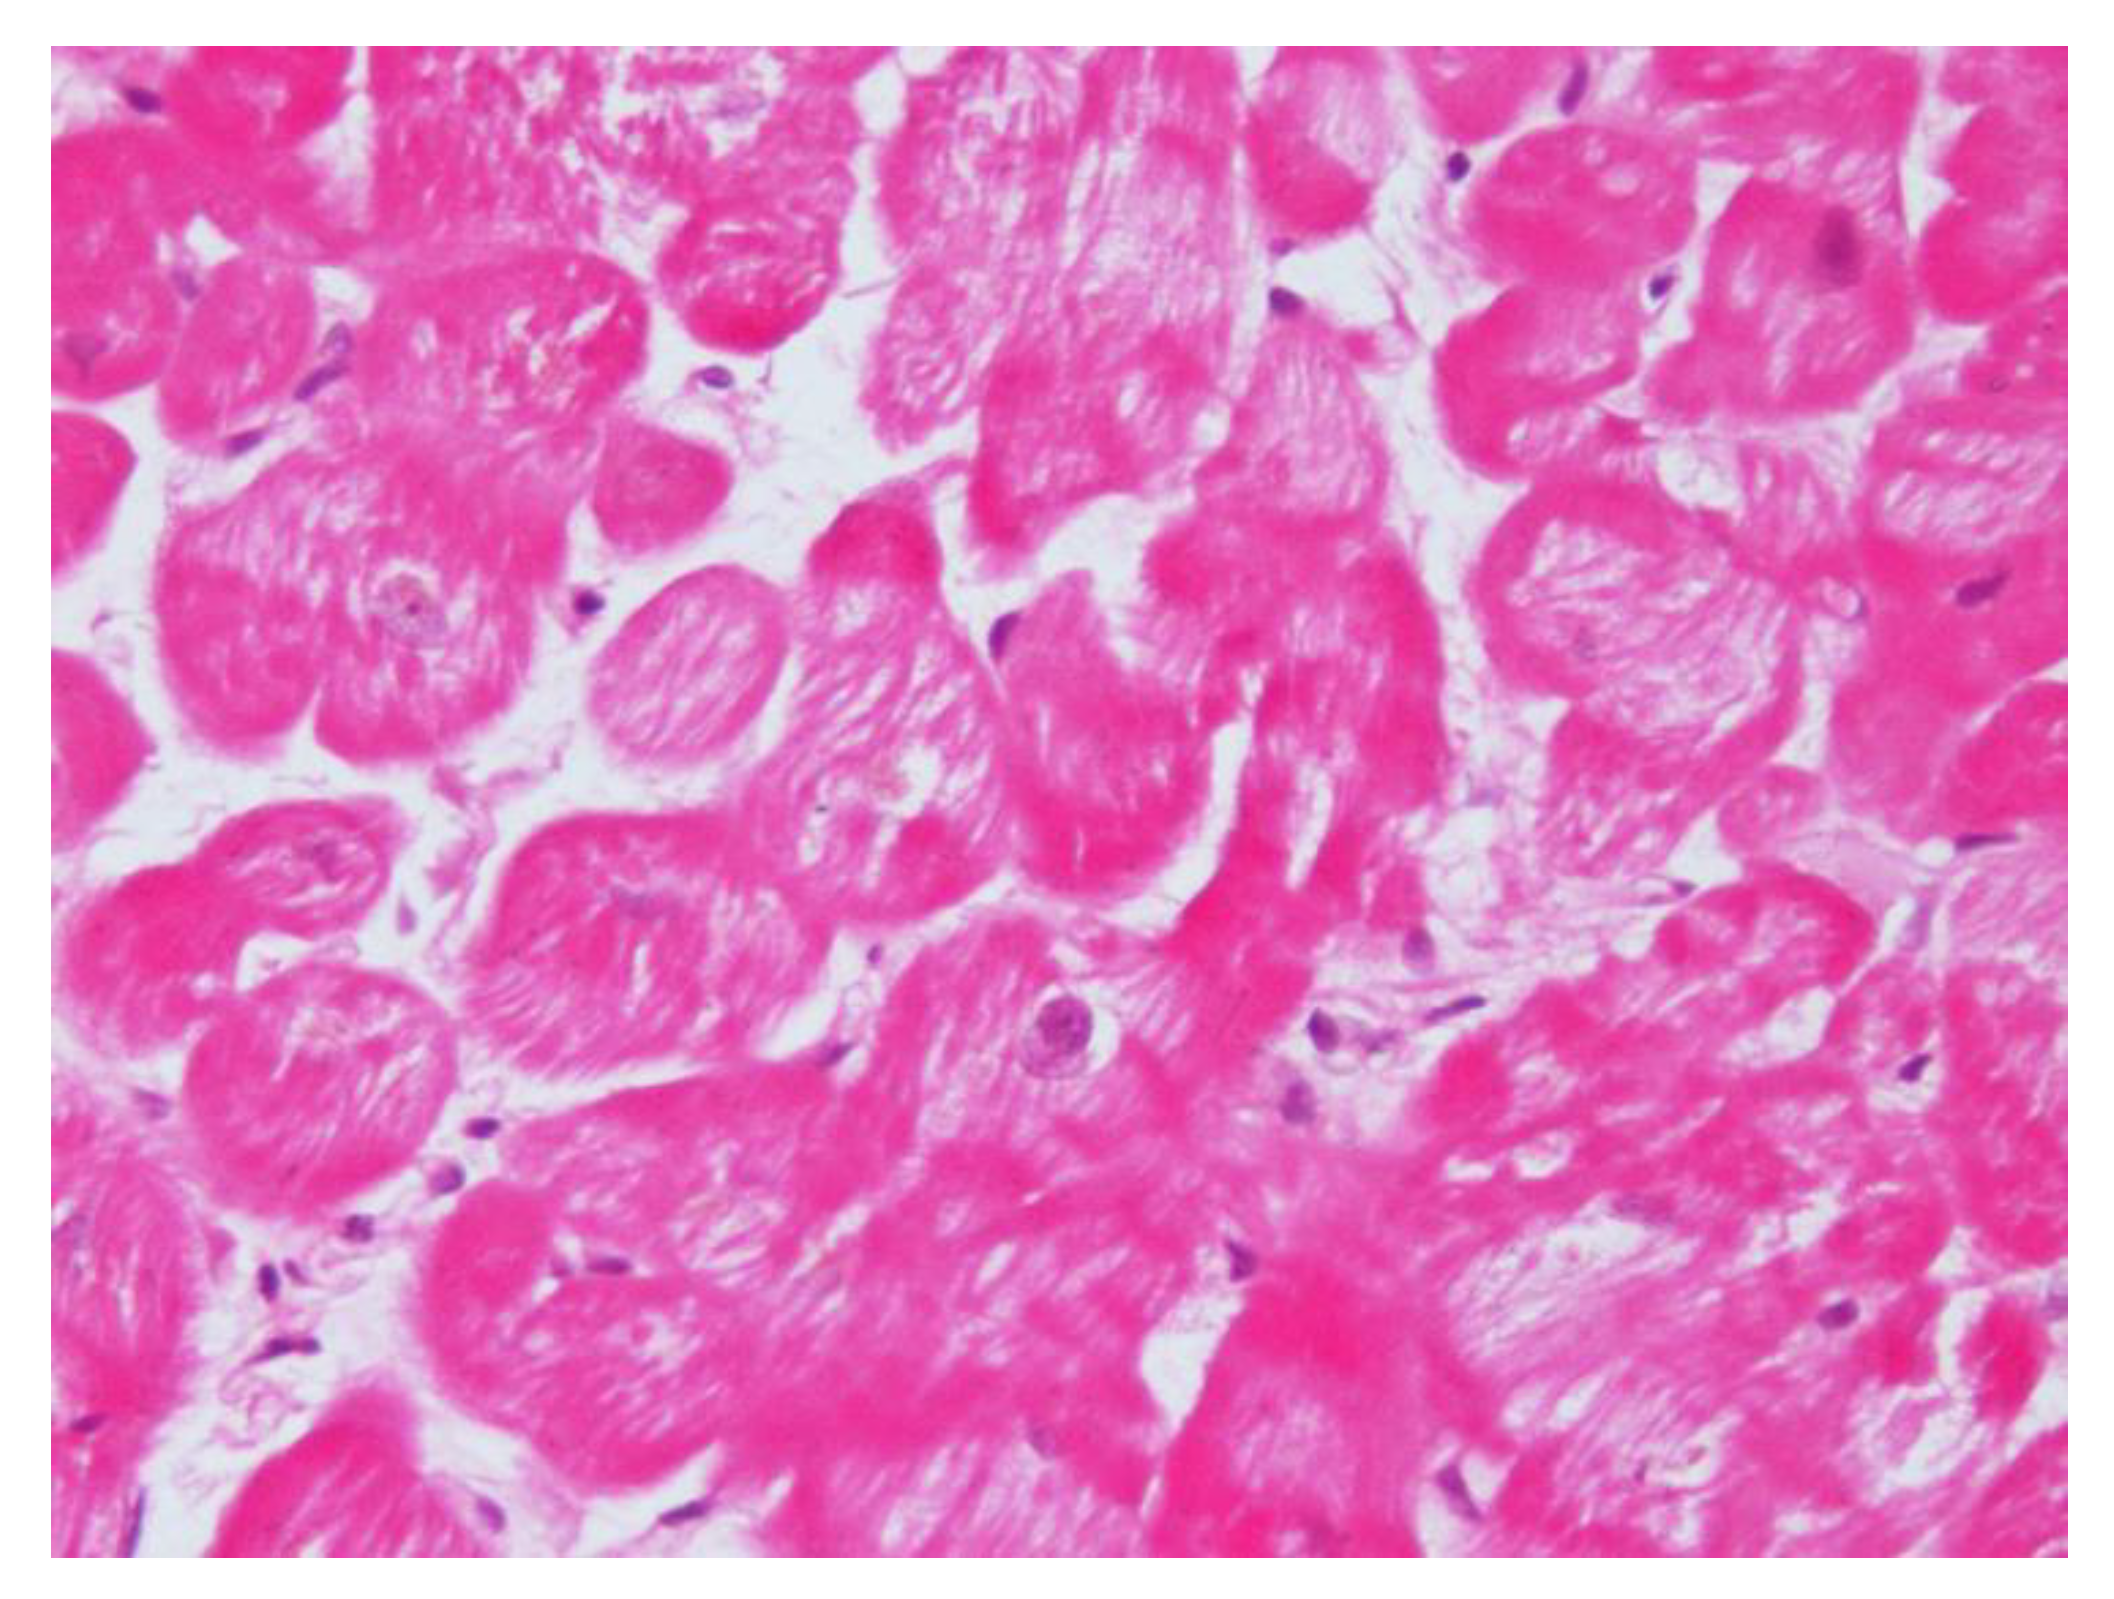

After their first observation, Frustaci et al., confirmed CS cardiomyopathy features in another eight patients with dilatative cardiomyopathy due to cortisol-secreting adrenal adenoma [39], concluding that CS cardiomyopathy shares in common the following features: cardiomyocyte hypertrophy, myofibrillolysis, and myocardial fibrosis (Figure 2). A pathophysiological link is involved in the pressure overload and glucocorticoid-mediated augmentation of angiotensin II that are jointly responsible for cell hypertrophy. Cardiomyocytes’ response to angiotensin II is enhanced. Cell myofibrillolysis is directly and strictly related to the enhanced myocardial expression of atrogin-1, as its expression was enhanced more than 38-fold during heart failure.

Increased plasma cortisol levels determine the activation of forkhead box (FOXO) transcription factors, with the subsequent activation of proteasome proteolysis, myofibrillolysis, and cell death [40]. Atrogin-1 returns to physiological levels after the treatment of cortisol excess and the restoration of cardiac damage, and it is also associated with a significant decrease in myofibrillolysis cell area from 61 to 22%. All these data confirm the effects of glucocorticoids on skeletal and cardiac muscle atrophy previously obtained in experimental models.

Figure 2. Hematoxylin and eosin staining (200×) shows a reduction in contractile elements because of gluconeogenesis due to cortisol overproduction in Cushing’s syndrome.